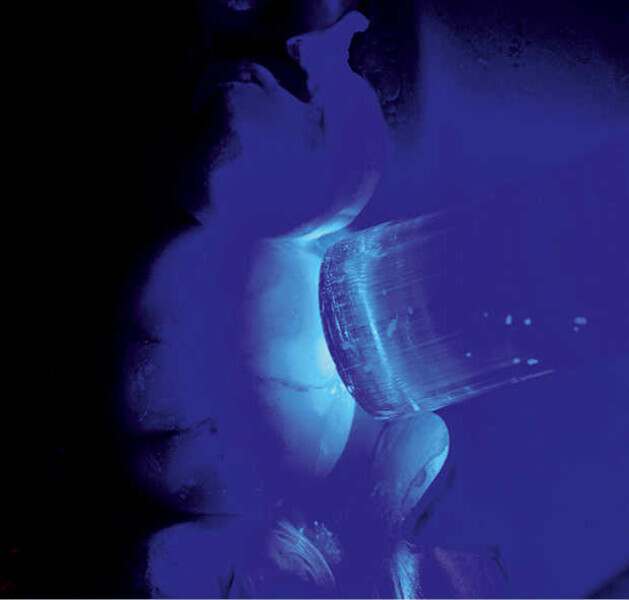

Fig. 5. Grabado y silanizado con Monobond Etch & Prime.